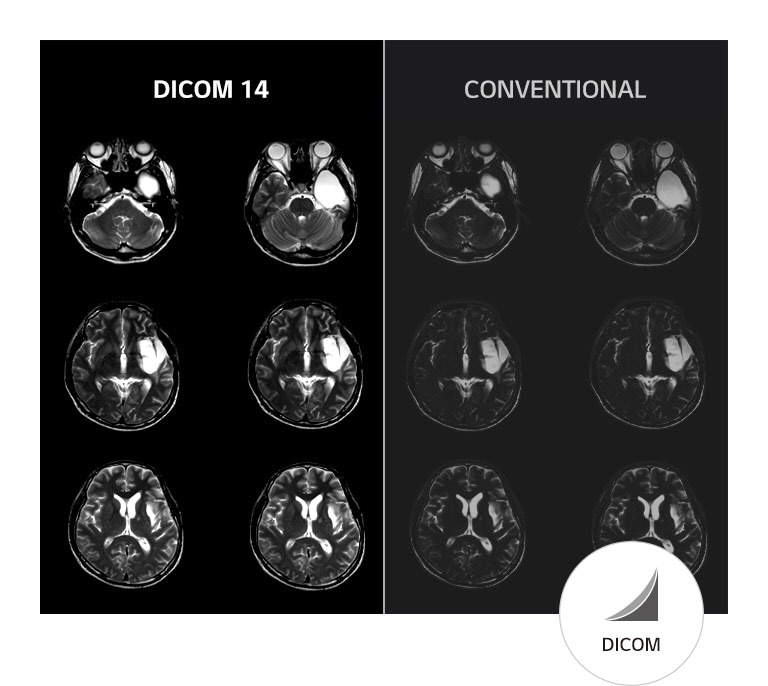

Reliable Image for Diagnosis

*Image for illustration purpose only.